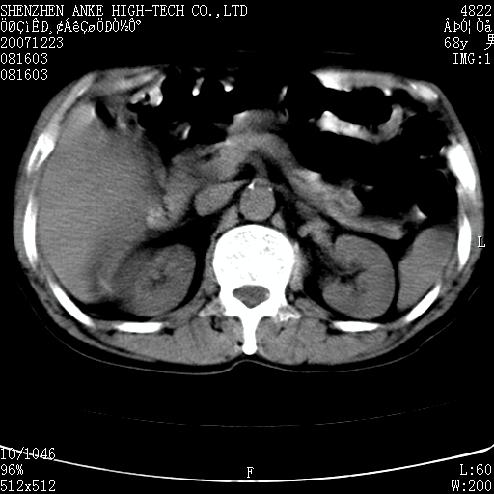

患者:男,63岁,2年前胆囊切除术后,现右上腹部剧烈疼痛近2天.

有无外伤史?右肾包膜下血肿可疑。

主要是问右肾有没有问题?患者无明显外伤史.

未见异常,病人差闭气,伪影较多.

肠道准备不好,干扰影大。

肠道气体伪影干扰太大了,应该是干扰所致,未见明显异常。

肠道准备不好,胃底后壁显示不清,右肾改变考虑为伪影。